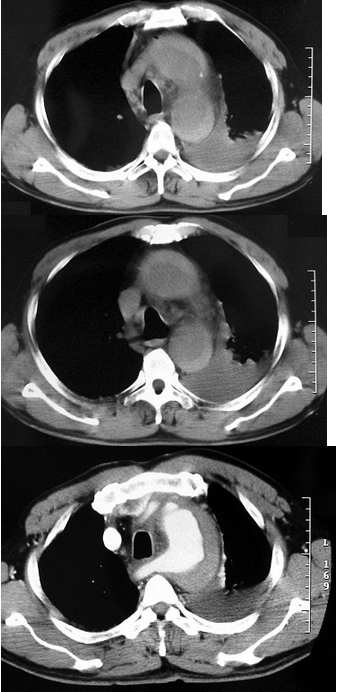

男,32岁,干咳,呼吸困难半月余,2月前被诊断为艾滋病,结合影像学检查,最可能的诊断是( )

A:肺结核

B:卡氏肺囊虫性肺炎

C:肺癌

D:大叶性肺炎

E:间质性肺炎